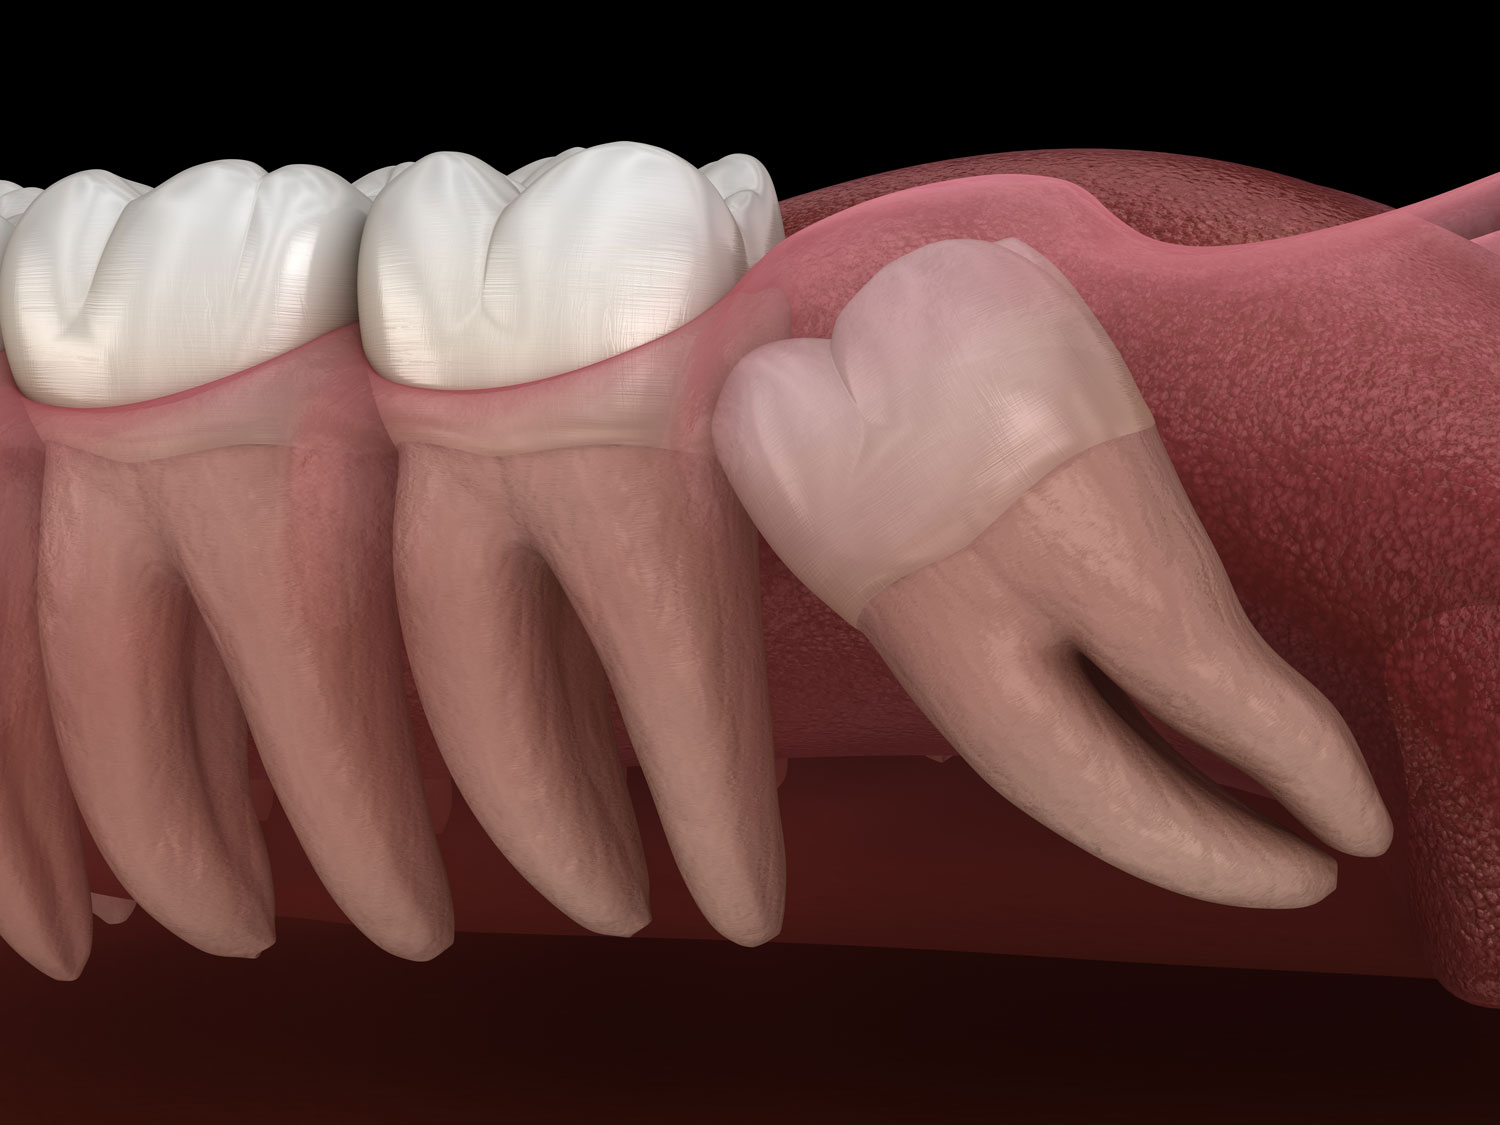

This is the most common situation when surgical protocol is used for extraction. This does refer to the wisdom teeth that are fully or partially impacted in the jaw bone.

Because of the lack of space, wisdom teeth can sometimes emerge at an angle or get stuck and only partially emerge. Wisdom teeth that grow through like this are known as impacted.